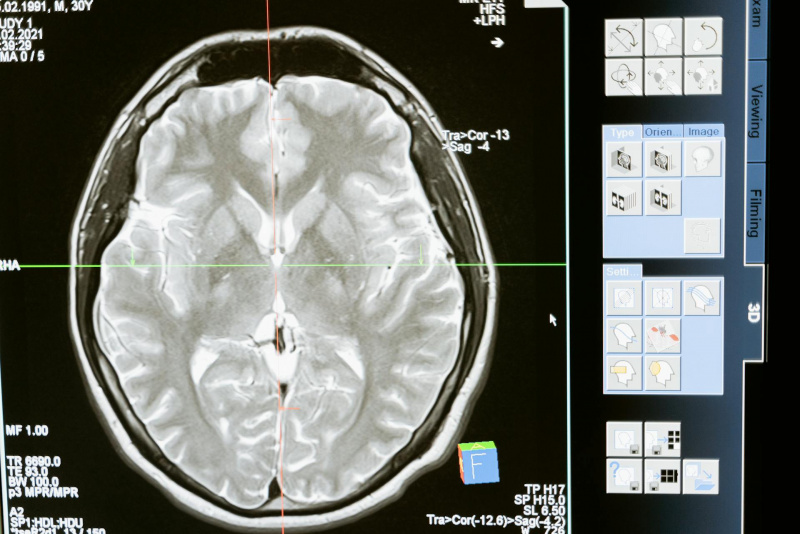

Le cellule staminali neurali svolgono un ruolo essenziale nel mantenere la funzionalità del cervello, generando nuovi neuroni e riparando i danni. Tuttavia, con l'età, queste cellule perdono la loro capacità rigenerativa, riducendo la produzione di nuovi neuroni, il che contribuisce al declino cognitivo e alla perdita di memoria tipica delle malattie neurodegenerative. Fino ad oggi, la sfida è stata trovare un modo per ripristinare questa capacità rigenerativa nelle cellule staminali cerebrali adulte.

Questo studio apre nuove prospettive nella ricerca di terapie rigenerative per il cervello umano. Se i risultati saranno confermati anche negli esseri umani, questa tecnica potrebbe fornire una base per trattamenti che rallentano o addirittura fermano il declino cognitivo legato all'età e alle malattie neurodegenerative. La possibilità di riattivare le cellule staminali neurali e aumentare la neurogenesi potrebbe contribuire a preservare la memoria, la capacità cognitiva e la funzionalità cerebrale complessiva.